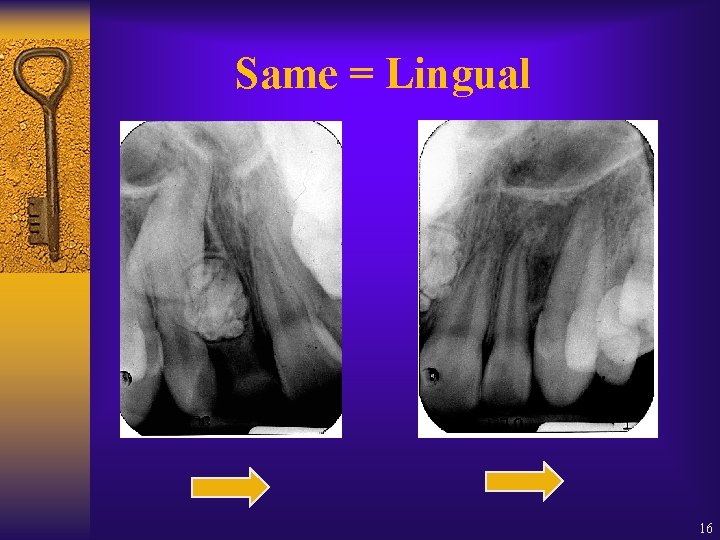

Same = Lingual 16